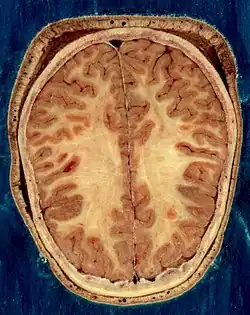

Головной мозг человека занимает почти всю полость мозгового отдела черепа, кости которого защищают головной мозг от внешних механических повреждений. В процессе роста и развития головной мозг принимает форму черепа.

Объём мозга большинства людей находится в пределах 1250—1600 кубических сантиметров и составляет 91—95 % ёмкости черепа. В головном мозге различают пять отделов: продолговатый мозг; задний, включающий в себя мост, мозжечок и эпифиз; средний; промежуточный; и передний мозг, представленный большими полушариями. Наряду с приведённым выше делением на отделы, весь мозг разделяют на три большие части:

Кора большого мозга покрывает два полушария головного мозга: правое и левое.

Полушария большого мозга извне покрыты серым веществом, образующим кору большого мозга, или плащ. В коре насчитывается 15 млрд клеток, а если учесть, что каждая из них имеет от 7 до 10 тыс. связей с соседними клетками, то можно сделать вывод о гибкости, устойчивости и надёжности функций коры. Поверхность коры значительно увеличивается за счет борозд и извилин. Кора филогенетическая является самой большой структурой мозга, её площадь примерно 220 тысяч мм2.